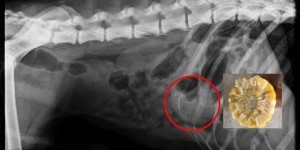

Tierarztpraxis Baba Gepp Vorsicht mit Maiskolben! Aus da ist meinem Hund noch nie was passiert und der spielt seit Jahren damit, kann schnell Ernst werden. Der Mais ist reif und die Ernte im vollen Gange. Die auf den Feldern liegenden Maiskolben sin...